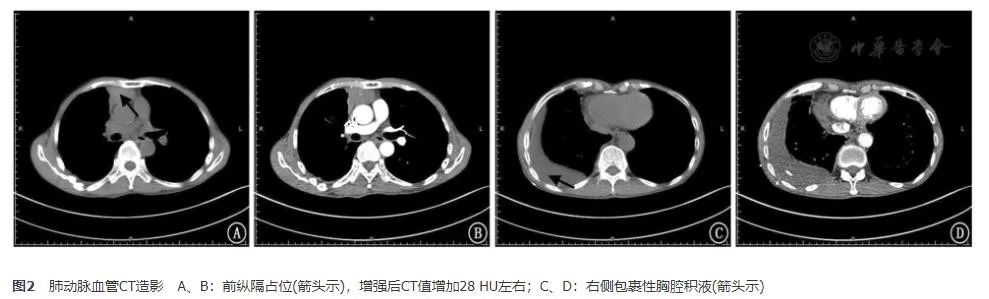

入院后查甲状腺及颈部淋巴结B超未见异常。肺通气灌注显像提示:右肺下叶前基底段、后基底段及左肺上叶尖后段多发通气与血流灌注降落灶(匹配);余双肺通气及血流灌注未见异常,无肺栓塞依据。经过胸腔抽液后,复查肺动脉血管CT造影(2017年11月24日)提示肺血管未见明显异常,前纵隔占位(增强后CT值增加28 HU左右);两肺下叶炎症、右侧胸腔积液,较前片(2017年11月15日)好转;两肺多发纤维灶,右肺上叶微小结节(图2)。

图2 肺动脉血管CT造影 A、B:前纵隔占位(箭头示),增强后CT值增加28 HU左右;C、D:右侧包裹性胸腔积液(箭头示)